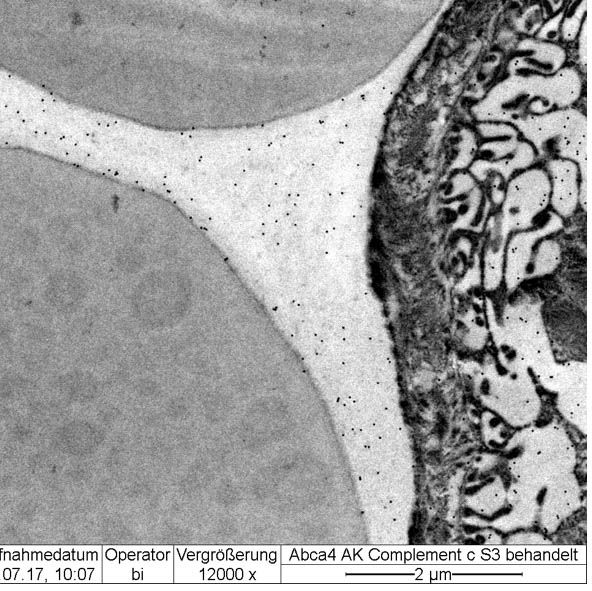

- Electron Microscope

- Electron Microscope